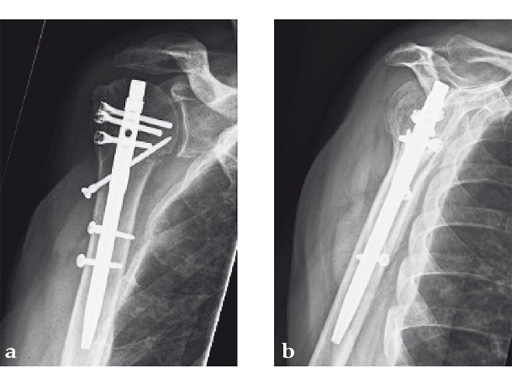

Case 3: Three-part varus displaced fracture with head-split component in a 60-year-old woman.

This case is an illustration of the application of the new nail in a borderline indication. Head-split fractures remain a challenge whatever implant is used for fixation.